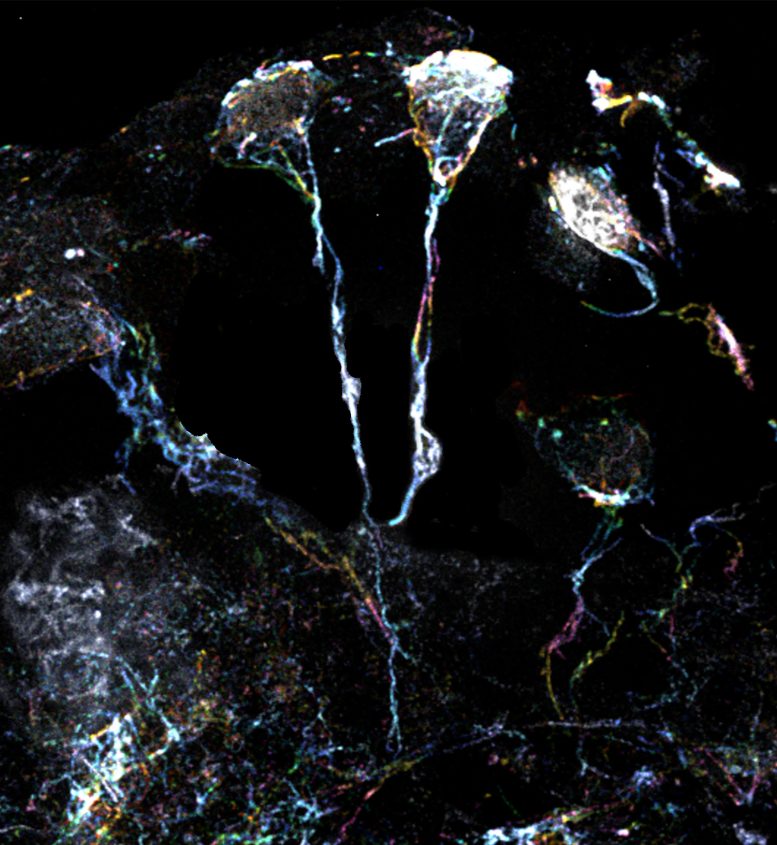

科學(xué)家團(tuán)隊(duì)使用放大倍數(shù)為10倍的超分辨率顯微鏡檢查了果蠅休眠神經(jīng)干細(xì)胞的標(biāo)志性微小纖維結(jié)構(gòu)。這些細(xì)微結(jié)構(gòu)的直徑約為1.5μm(比人類頭發(fā)的直徑小20倍),是從細(xì)胞體延伸出來(lái)的突起,富含肌動(dòng)蛋白或蛋白質(zhì)細(xì)絲。一種特定類型的Formin蛋白可以激活這些細(xì)絲并使其組裝。

果蠅大腦中處于休眠狀態(tài)的神經(jīng)干細(xì)胞具有富含肌動(dòng)蛋白絲的突起

果蠅大腦中處于休眠狀態(tài)的神經(jīng)干細(xì)胞具有富含肌動(dòng)蛋白絲的突起。圖片來(lái)源:杜克-新加坡國(guó)立大學(xué)醫(yī)學(xué)院